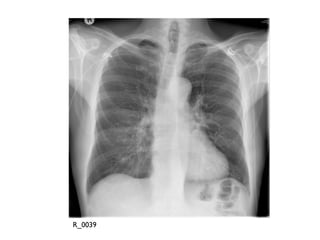

This document appears to be notes from an ECG talk that includes lab results, ABG values, and a quote from a poem by T.S. Eliot. It also mentions Wellens' syndrome and credits Dr. Smith's ECG Blog as the source. The document contains various identifiers but no clear narrative or context for the included information.